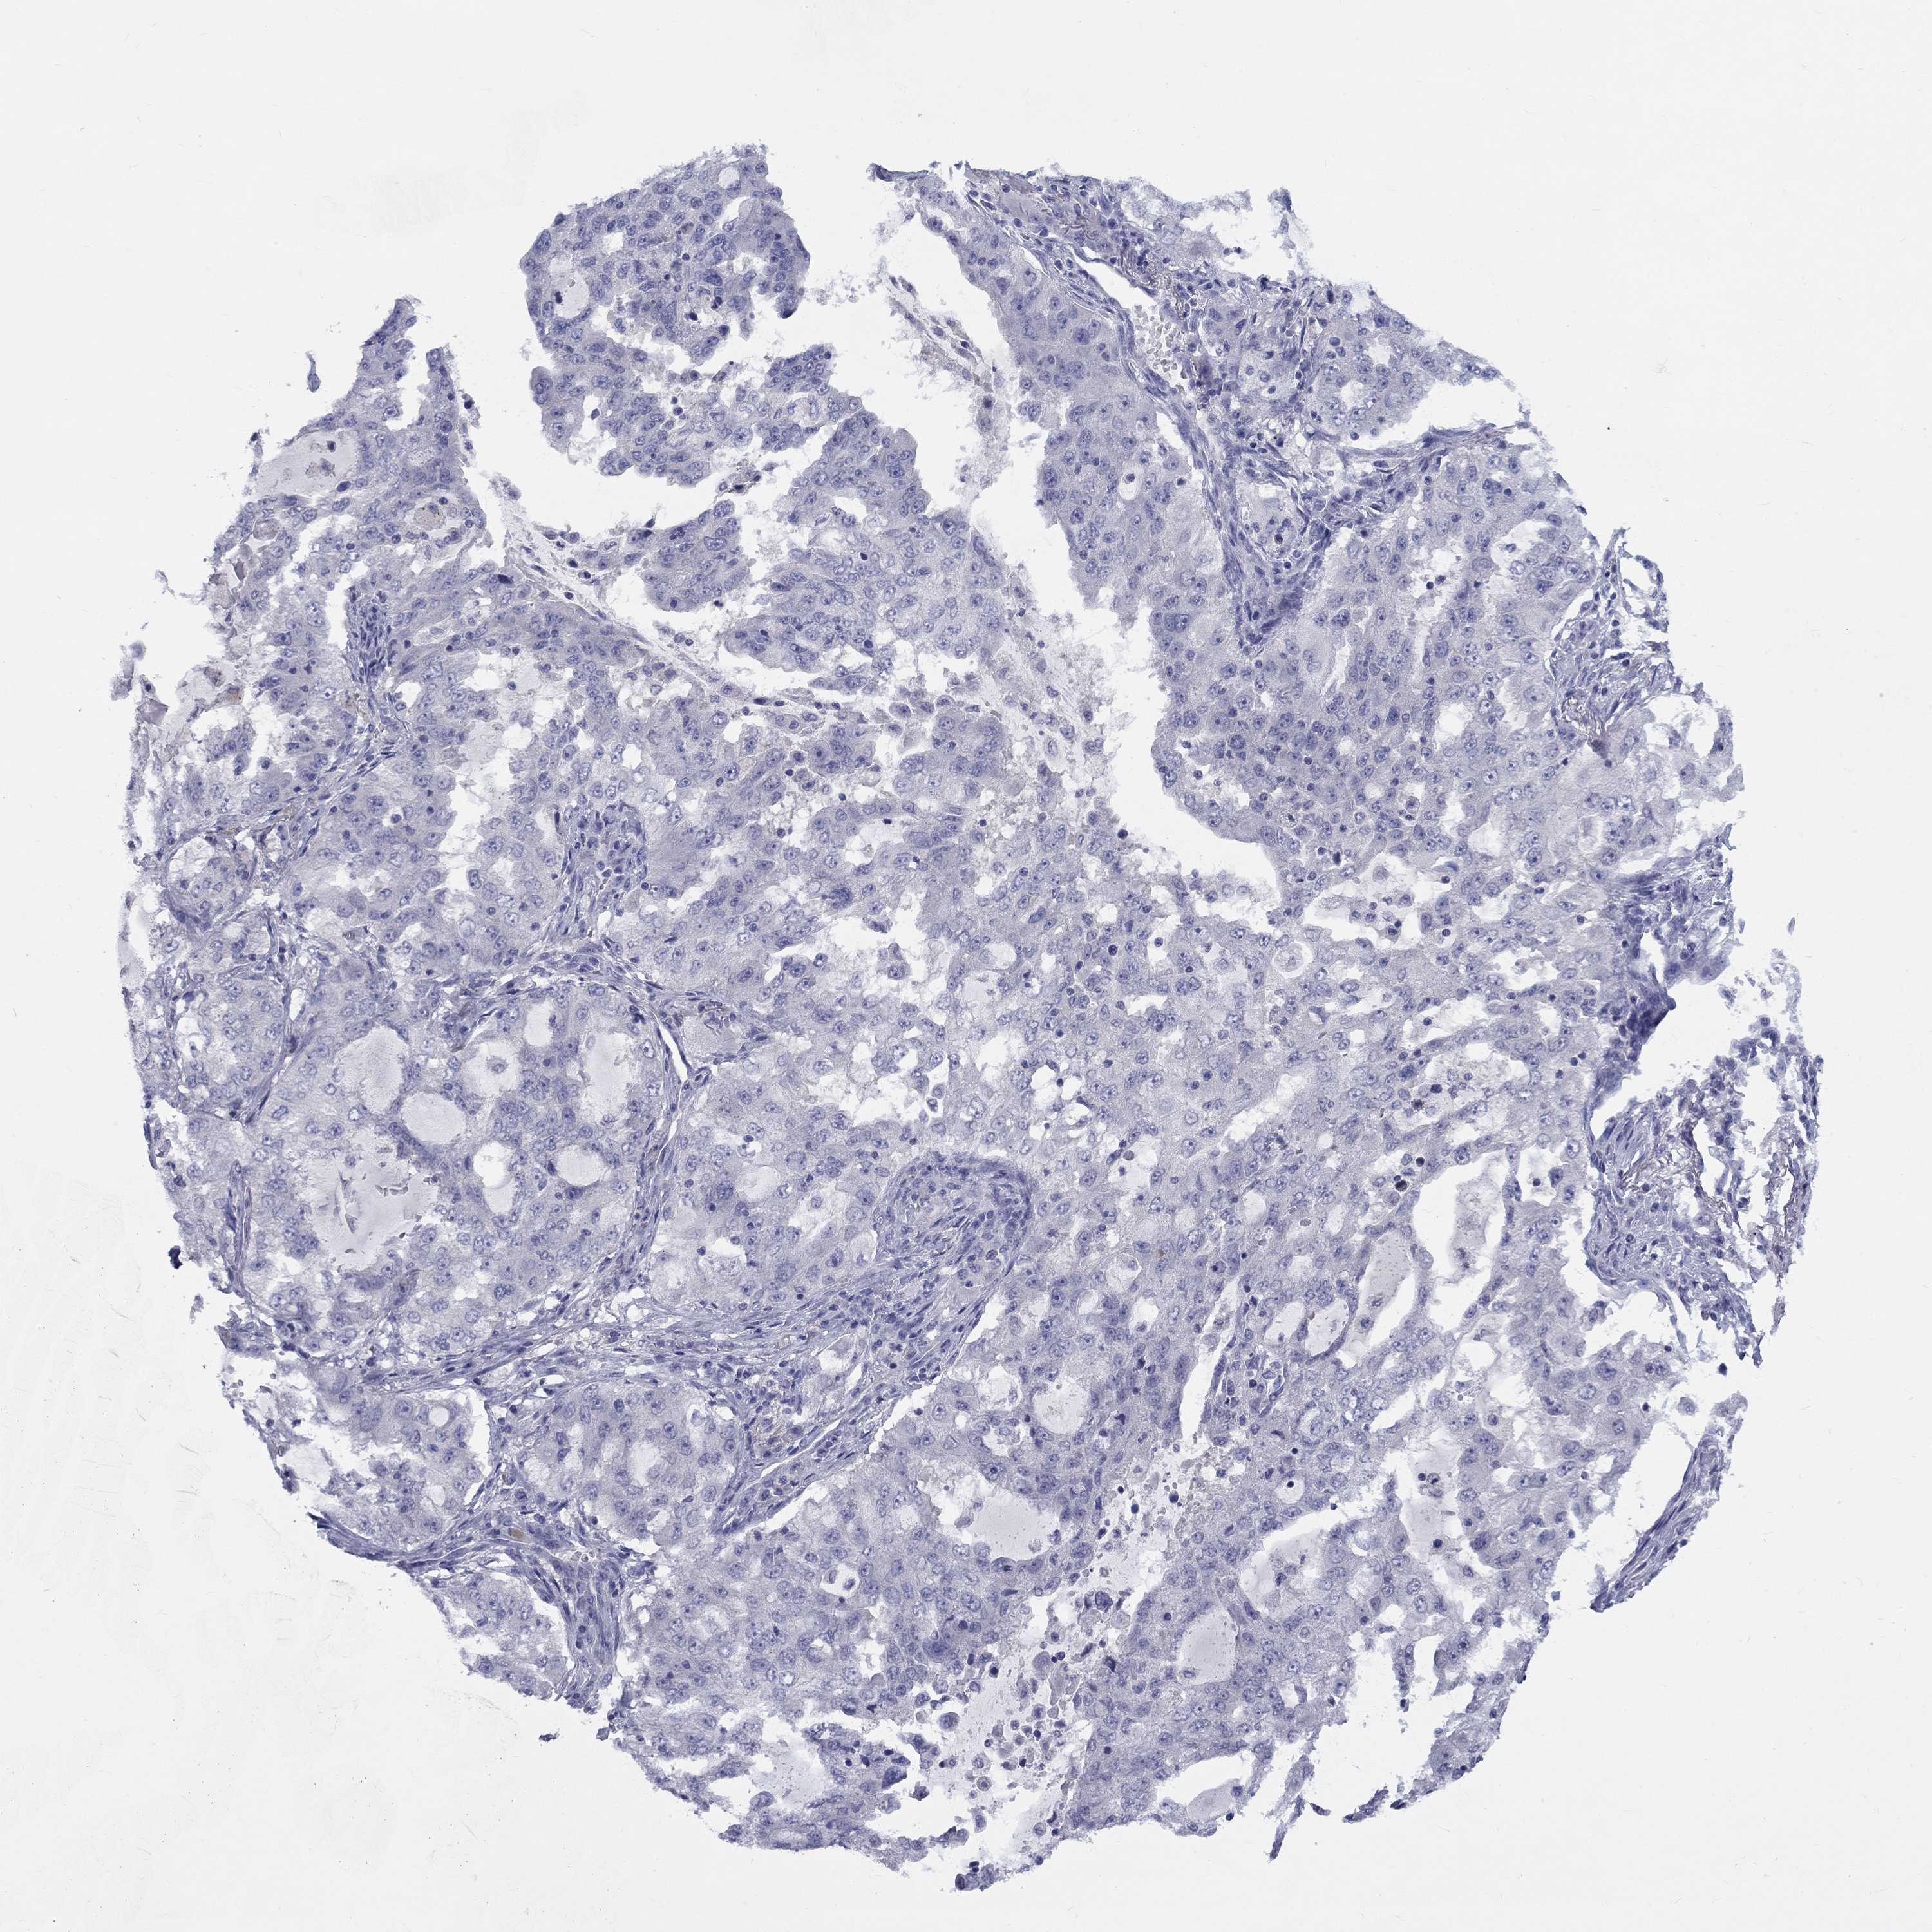

CANCER LUNG CANCER Show tissue menu

CACNA1A is not prognostic in Lung Adenocarcinoma (TCGA)

Average pTPM 0.6

Number of samples 497